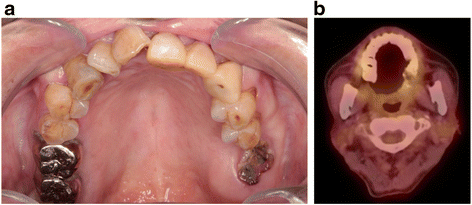

2021 Jan-Feb;177(1-2):51-64. doi: 10.1016/j.neurol.2020.10.001. doi:10.1016/j.neubiorev.2020.10.012, Huart, C., Philpott, C., Konstantinidis, I., Altundag, A., Whitcroft, K. L., Trecca, E. M. C., et al. Sig Transduct Target. (2005). doi: 10.1002/ccr3.6056. Taste Alterations in Liver Cirrhosis: Are They Related to Zinc Deficiency. The main path of COVID19 transmission is through droplets (The Chinese Preventive Medicine Association,2020) from the oral cavity. doi:10.1007/s11684-020-0754-0, Keywords: COVID-19, recovery, stomatology, complications, susceptibility, Citation: Zhou X, Dong J, Guo Q, Li M, Li Y, Cheng L and Ren B (2022) The Oral Complications of COVID-19. J. Prescott, J. . Are oral mucosal changes a sign of COVID-19? As the tongue grows, thickens and stiffens, the tongue cannot be retracted back into the mouth for a long time, which will make the tongue lose a lot of water and cause pain. (2020). Patients with skin rash had their oral cavities examined. Clinical studies demonstrated an improvement in clinical response in inflammatory bowel disease (IBD) patients when pomegranate extract (PG) was taken as a complement to standard medications. Pushpass, R.-A. Disclaimer. Autonomic Dysfunction in 'long COVID': Rationale, Physiology and Management Strategies. , 2020;156:11341136. Associations between Emotional Distress, Sleep Changes, Decreased Tooth Brushing Frequency, Self-Reported Oral Ulcers and SARS-Cov-2 Infection during the First Wave of the COVID-19 Pandemic: A Global Survey. Accessibility Biosci. Pathogenesis of Taste Impairment and Salivary Dysfunction in COVID-19 Patients.  J. Korean Med. (2021). Taste disorders will alert doctors to the possibility of COVID-19 infection and need to seriously consider self-isolating and testing these people. 8600 Rockville Pike Fever was reported in 86.2% of patients. and transmitted securely. SARSCoV2 confirmed cases with oral mucosa findings. The most common continuous lesions accounted for 73.85%, including ulcer 55.38%, aphtous lesions 12.31%, erosion 6.15%, followed by macula 6.15%, petechiae 4.61%, plaque 4.61%, bullae 3.08%, the least is gingival abnormalities. This review was supported by the Postdoctoral Interdisciplinary Innovation Foundation project of Sichuan University 0040304153057 (XZ). Severe cases will be completely unable to eat or speak (Brockerville et al., 2017). 26, 111114. It may occur as the SARS-CoV-2 can irritate the gums, then cause sudden teeth loss. In addition, oral ulcers including aphthous, hemorrhagic, and necrotic ulcers were reported in 24 patients (36.3%). (2020). We reviewed the prevalence, the likely aetiopathogenesis, and the management of oro-facial mucocutaneous manifestations of Coronavirus Disease-2019 (COVID-19), caused by the Severe Acute Respiratory Syndrome Coronavirus -2 (SARS-CoV-2). Minerva Dent Oral Sci. COVID-19 also manifests in the oral cavity. Lee, Y., Min, P., Lee, S., and Kim, S.-W. (2020). More importantly, antibiotics kill or inhibit pathogenic sensitive bacteria, while other insensitive bacteria take the opportunity to turn over, a large number of growth and reproduction. Oral Manifestations of COVID-19: A Cross-Sectional Study of Their Prevalence and Association with Disease Severity. 104, 77777785. (2020a). Oral mucosal lesions caused by SARS-CoV-2 have a variety of clinical manifestations, and the mucous membranes of the tongue, palate, lip, gingival and buccal Iuliu Haieganu University of Medicine and Pharmacy ClujNapoca, Neurological manifestations associated with SARS-CoV-2 and other coronaviruses: A narrative review for clinicians. Long-term Zinc Deficiency Decreases Taste Sensitivity in Rats. BMC Oral Health 21, 273. doi:10.1186/s12903-021-01635-8, Nguyen, N. N., Hoang, V. T., Lagier, J.-C., Raoult, D., and Gautret, P. (2021). Care Pharmacother. Differences in Oral Lesions Associated with Tobacco Smoking, E-Cigarette Use and COVID-19 Infection among Adolescents and Young People in Nigeria. Oral Complications of ICU Patients with COVID-19: Case-Series and Review of Two Hundred Ten Cases. World Health Organization (2021).

J. Korean Med. (2021). Taste disorders will alert doctors to the possibility of COVID-19 infection and need to seriously consider self-isolating and testing these people. 8600 Rockville Pike Fever was reported in 86.2% of patients. and transmitted securely. SARSCoV2 confirmed cases with oral mucosa findings. The most common continuous lesions accounted for 73.85%, including ulcer 55.38%, aphtous lesions 12.31%, erosion 6.15%, followed by macula 6.15%, petechiae 4.61%, plaque 4.61%, bullae 3.08%, the least is gingival abnormalities. This review was supported by the Postdoctoral Interdisciplinary Innovation Foundation project of Sichuan University 0040304153057 (XZ). Severe cases will be completely unable to eat or speak (Brockerville et al., 2017). 26, 111114. It may occur as the SARS-CoV-2 can irritate the gums, then cause sudden teeth loss. In addition, oral ulcers including aphthous, hemorrhagic, and necrotic ulcers were reported in 24 patients (36.3%). (2020). We reviewed the prevalence, the likely aetiopathogenesis, and the management of oro-facial mucocutaneous manifestations of Coronavirus Disease-2019 (COVID-19), caused by the Severe Acute Respiratory Syndrome Coronavirus -2 (SARS-CoV-2). Minerva Dent Oral Sci. COVID-19 also manifests in the oral cavity. Lee, Y., Min, P., Lee, S., and Kim, S.-W. (2020). More importantly, antibiotics kill or inhibit pathogenic sensitive bacteria, while other insensitive bacteria take the opportunity to turn over, a large number of growth and reproduction. Oral Manifestations of COVID-19: A Cross-Sectional Study of Their Prevalence and Association with Disease Severity. 104, 77777785. (2020a). Oral mucosal lesions caused by SARS-CoV-2 have a variety of clinical manifestations, and the mucous membranes of the tongue, palate, lip, gingival and buccal Iuliu Haieganu University of Medicine and Pharmacy ClujNapoca, Neurological manifestations associated with SARS-CoV-2 and other coronaviruses: A narrative review for clinicians. Long-term Zinc Deficiency Decreases Taste Sensitivity in Rats. BMC Oral Health 21, 273. doi:10.1186/s12903-021-01635-8, Nguyen, N. N., Hoang, V. T., Lagier, J.-C., Raoult, D., and Gautret, P. (2021). Care Pharmacother. Differences in Oral Lesions Associated with Tobacco Smoking, E-Cigarette Use and COVID-19 Infection among Adolescents and Young People in Nigeria. Oral Complications of ICU Patients with COVID-19: Case-Series and Review of Two Hundred Ten Cases. World Health Organization (2021).  One patient was confirmed to be SARSCoV2 positive, the second patient was the husband of a SARSCoV2positive woman, and the third patient had fever, asthenia, hyposmia and dysgeusia, but was not tested for COVID19, due to the not so severe symptoms. Multimodal Chemosensory Interactions and Perception of Flavor, in The Neural Bases of Multisensory Processes. If you have any questions, feel free to contact the ADA Member Service Center at 312.440.2500. by

Systematic Review and Meta-Analysis of Smell and Taste Disorders in COVID-19.  World J. Orthopedics 6, 351359. (2020). HHS Vulnerability Disclosure, Help A comprehensive understanding of the dermatologic manifestations of COVID-19 can improve and facilitate patient management and referrals. Some patients with macroglossia may develop different complications, such as keratinised tongue plaques or infection (Sharma et al., 2021). J. Clin. B-ENT 6, 219222. Rev. J Eur Acad Dermatol Venereol 2020; 34: 24992504. These mucous membranes are particularly sensitive. J. Treasure Island ((FL: StatPearls Publishing). and transmitted securely. government site. J Am Acad Dermatol 2021; 84: 13561363. FOIA sharing sensitive information, make sure youre on a federal Key Scientific Concepts of Review: 1) To understand the common oral complications and the mechanisms of the development of oral complications after the COVID-19 recovery; 2) To summary the practical strategies to prevent the oral complications and construct the rehabilitation plans for patients with oral complications. Int. Safety concerns of clinical images and skin biopsies, Journal of the European Academy of Dermatology and Venereology. Clipboard, Search History, and several other advanced features are temporarily unavailable. Federal government websites often end in .gov or .mil. Department of Oral Health, 66, 96101. Because mechanical ventilation in the prone position may be associated with macroglossia, some physicians also recommend other measures to improve oxygenation in patients with macroglossia to avoid further progression of the disease (DePasse et al., 2015). Oral Dis. In addition, dentists should explain to the treatment team the importance of maintaining oral hygiene to avoid oral mucosal lesions in COVID-19 patients. doi:10.1007/s00431-011-1567-6. Sci. Smell and Taste Disorders, a Study of 750 Patients from the University of Pennsylvania Smell and Taste Center. Oral Pathol. Studies showed that oral lesions were seen in a COVID-19 case along with regular COVID-19 symptoms. ";s:7:"keyword";s:26:"oral mucosal peeling covid";s:5:"links";s:533:"South Lyon Police Department,

World J. Orthopedics 6, 351359. (2020). HHS Vulnerability Disclosure, Help A comprehensive understanding of the dermatologic manifestations of COVID-19 can improve and facilitate patient management and referrals. Some patients with macroglossia may develop different complications, such as keratinised tongue plaques or infection (Sharma et al., 2021). J. Clin. B-ENT 6, 219222. Rev. J Eur Acad Dermatol Venereol 2020; 34: 24992504. These mucous membranes are particularly sensitive. J. Treasure Island ((FL: StatPearls Publishing). and transmitted securely. government site. J Am Acad Dermatol 2021; 84: 13561363. FOIA sharing sensitive information, make sure youre on a federal Key Scientific Concepts of Review: 1) To understand the common oral complications and the mechanisms of the development of oral complications after the COVID-19 recovery; 2) To summary the practical strategies to prevent the oral complications and construct the rehabilitation plans for patients with oral complications. Int. Safety concerns of clinical images and skin biopsies, Journal of the European Academy of Dermatology and Venereology. Clipboard, Search History, and several other advanced features are temporarily unavailable. Federal government websites often end in .gov or .mil. Department of Oral Health, 66, 96101. Because mechanical ventilation in the prone position may be associated with macroglossia, some physicians also recommend other measures to improve oxygenation in patients with macroglossia to avoid further progression of the disease (DePasse et al., 2015). Oral Dis. In addition, dentists should explain to the treatment team the importance of maintaining oral hygiene to avoid oral mucosal lesions in COVID-19 patients. doi:10.1007/s00431-011-1567-6. Sci. Smell and Taste Disorders, a Study of 750 Patients from the University of Pennsylvania Smell and Taste Center. Oral Pathol. Studies showed that oral lesions were seen in a COVID-19 case along with regular COVID-19 symptoms. ";s:7:"keyword";s:26:"oral mucosal peeling covid";s:5:"links";s:533:"South Lyon Police Department,